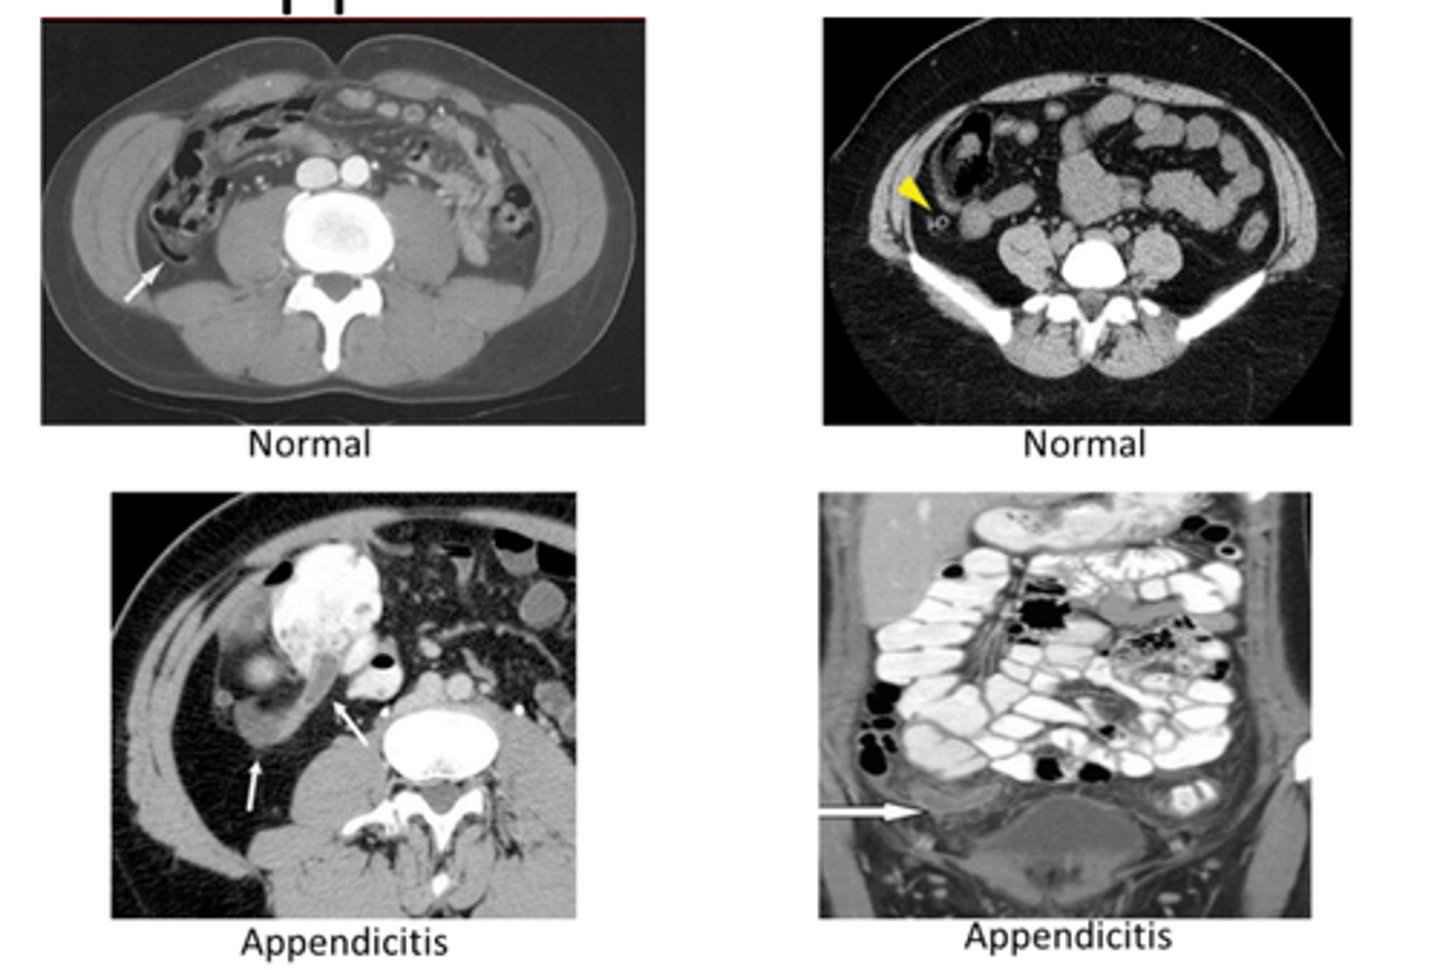

appendicitis

obstruction of appendix by a fecalith, inflammation, foreign body, or neoplasm -> leads to increased intraluminal pressure, venous congestion, infection and thrombosis of intramural vesses

S/Sx: vague pain, pain shift to RLQ, N/V, low fever

appendicitis imaging

CT- diagnostic study of choice in adults, dilated appendix that does not fill w oral contrast, periappendiceal inflammation, increased contrast enhancement of wall, perforation

US- diagnostic study of choice in pediatric pts

appendix

can be seen where it joins cecum, often not seen on CT